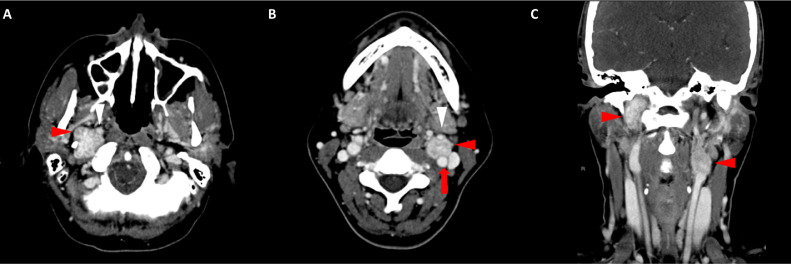

胸部、腹部和骨盆的对比增强动脉和静脉期 CT 显示多个圆形、主要是血管丰富的异质肿块,具有囊性和实性成分,起源于胃底和胃体(图 2-4)。 病变部分呈外生结构,被认为位于粘膜下层。 在颈部多发同步性副神经节瘤的情况下,最初的鉴别诊断包括多发性副神经节瘤、多发性 GIST 以及转移性疾病。

图 2:多发胃肠道间质瘤的轴位 CT 图像。 (A 和 B)轴位动脉相增强 CT 图像和(C 和 D)轴位静脉相增强 CT 图像显示多个圆形、不均匀、增强的肿块,具有实性和囊性成分。 肿块位于粘膜下,结构呈外生。